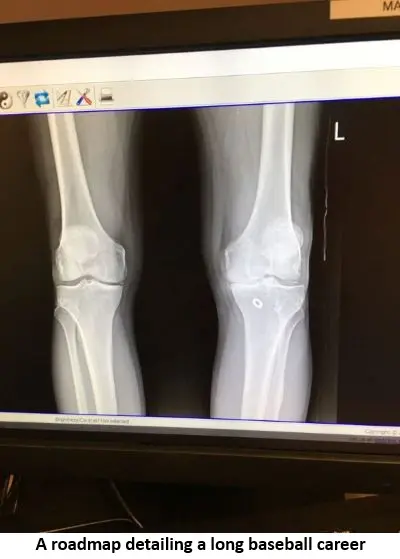

“I’m retiring from the league because my body won’t take it anymore, especially as a catcher. In the early 90’s, there was a game, and I was rounding third and heading home and tried to score,” explained Mike. “There was a bump under the grass and my heel hit the hump and my knee hyperextended backwards with a loud crack and I went down. I had to eventually give up catching and now primarily pitch but I’ve lived with this pain long enough. I promised my wife that this is the final year. It’s time to go under the knife and get the knee replaced.”